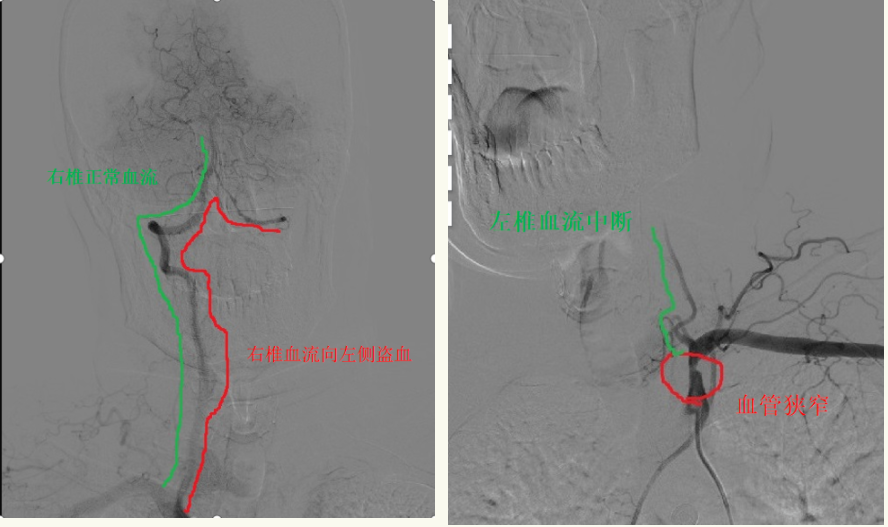

刘忠锦副院长经过仔细的问诊、查体后和家属详细的进行了沟通,患者选择相信附属一院的技术,决定住院进行手术治疗。入院后刘忠锦副院长带领神经介入团队及神经内五科医生认真地查房及阅片,经全脑血管造影诊断为左侧锁骨下动脉重度狭窄、锁骨下动脉盗血综合征,并制定了手术方案。

6月12日,经过完善的术前准备后,刘忠锦副院长带领神经介入团队为患者行锁骨下动脉支架植入术,术后支架形态良好,前向血流恢复,左侧椎动脉血流较手术前明显改善,且无并发症发生。

术后恢复正向血流